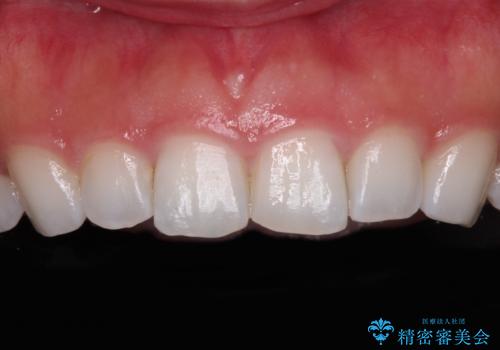

- 矯正治療で歯列を整えた後、前歯の形が気になった患者様です。

矯正前の歯列の影響で、前歯の先端が非対称にすり減ってしまったため、矯正治療後の形が非対称になっていました。

むし歯はなく、矯正治療で咬み合わせが改善していたので、侵襲量の少ないラミネートベニアにて治療することとしました。